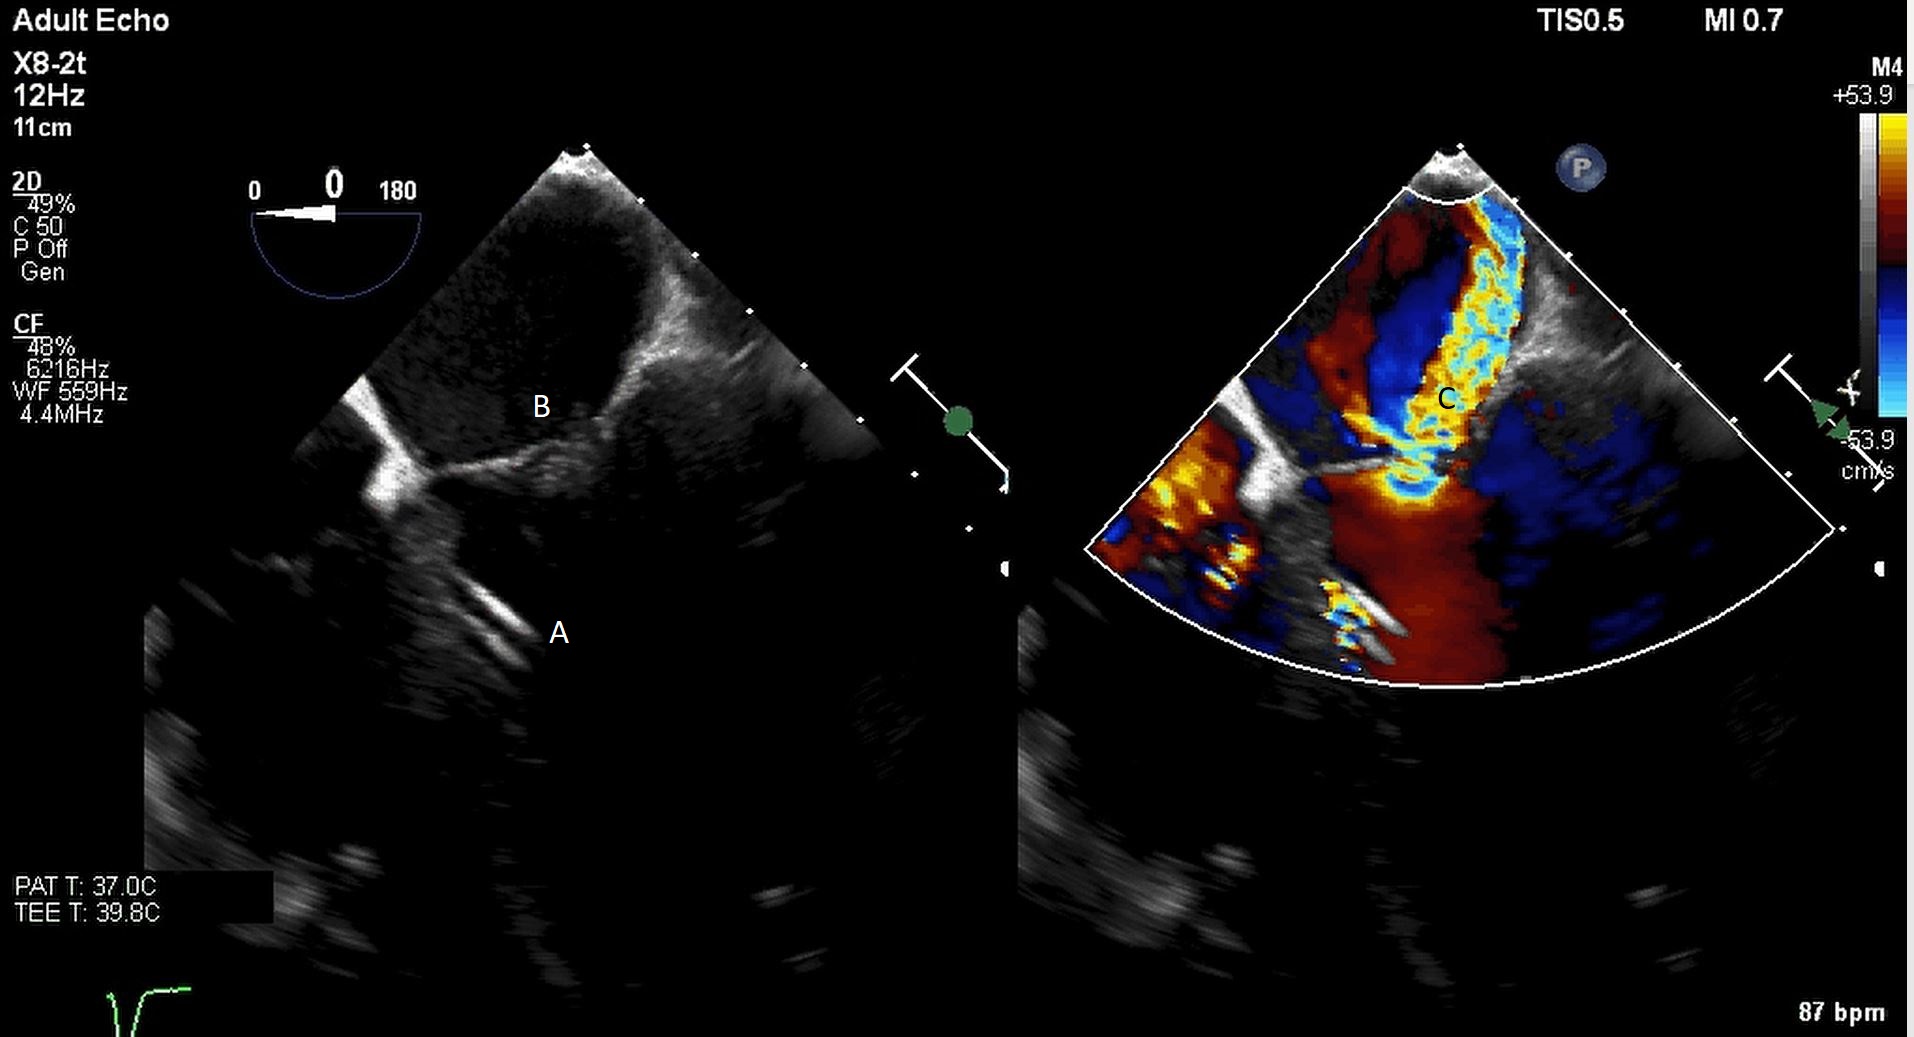

The TandemHeart Protek Duo is a percutaneous right ventricular assist device (RVAD) placed via a dual-lumen 29 French sheath in the right internal jugular vein. The inflow lumen is situated in the right atrium and outflow lumen in the main pulmonary artery. The port lumens are connected externally to a TandemHeart centrifugal pump [31]. As this is generally placed in the operating room, intra-operative TEE can be used to help guide placement. Similar to the Impella RP, bicaval and midesophageal 4 chamber views can visualize the inflow cannula and RV inflow-outflow view and upper esophageal views can be used to visualize the outflow cannula (Figs. 13,14,15). On occasion, its placement can result in distortion of the tricuspid valve morphology with resultant tricuspid regurgitation (Fig. 16). If this is noted, cannula repositioning can be considered. TEE can also help in identifying the ideal pump speed for a patient on TPD support. When utilizing a “ramp protocol”, where the pump speed is progressively increased intraoperatively, midline interventricular septal position can indicate an appropriate amount of RV support [32].

Fig. 13.A bicaval view on a TEE done during placement of a Protek Duo. The inflow lumen is seen entering the right atrium from the SVC. (A) Left atrium. (B) Right atrium. (C) Interatrial septum. (D) Protek Duo inflow lumen.

Fig. 14.Color flow imaging demonstrating a mosaic pattern at the inflow port. The interatrial septum and left atrium are also visualized. Note that no blood flow is being entrained from the left atrium across the inter atrial septum. (A) Left atrium. (B) Inflow port in the right atrium. (C) Mosaic pattern at the inflow port on color flow doppler.

Fig. 15.Real time 3D TEE imaging of the RV inflow outflow view demonstrating the Protek Duo in the RVOT. (A) Protek Duo. (B) RVOT. (C) Aortic valve.

Protek Duo (A) visualized in RV. Its placement caused disruption of tricuspid valve with resultant tricuspid regurgitation seen on color flow imaging (B).